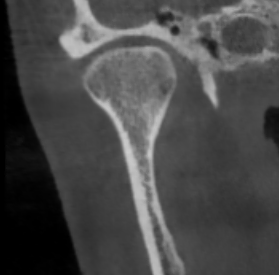

У здорового височно-нижнечелюстного сустава суставные поверхности гладкие и ровные. Такие суставы, как правило, восстанавливаются быстро.

Но, ко мне приходят пациенты с изменёнными суставными поверхностями в виде артроза. Эти суставы повреждены, и в них нарушено нормальное вращение.

Часто в таких случаях пациентам требуется помощь челюстно-лицевого хирурга. Тогда с пациентом работают два доктора: я — гнатолог и челюстно-лицевой хирург.